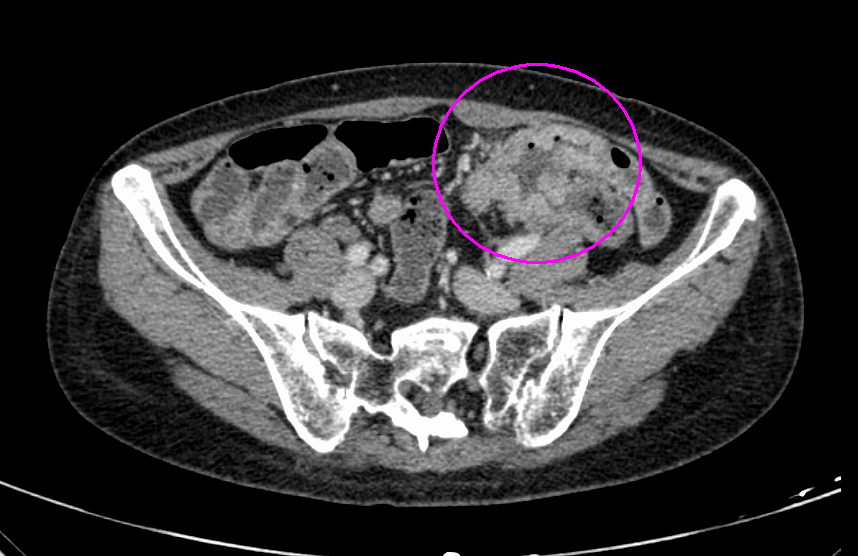

CT検査

CT検査画像

大腸がんに対してTNT療法を行った例

治療前

治療後